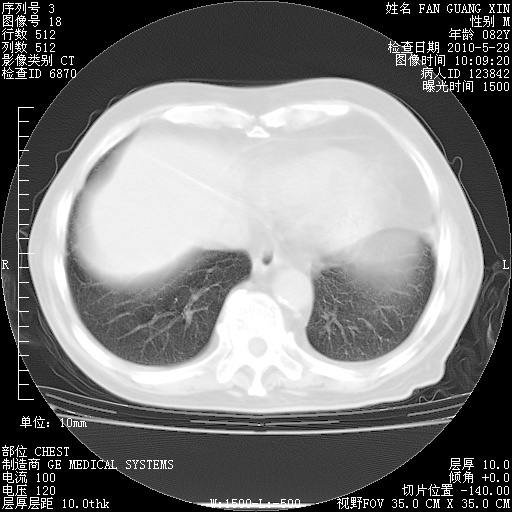

再治疗10天后的肺部CT

再治疗10天后的肺部CT 纵膈窗

阅读此次胸部CT,肺间质渗出性改变较入院时有吸收。目前从体温、白细胞、中性分叶明显增高,肯定存在细菌感染(发生医院感染哦,若无消化道及泌尿系统等感染的依据,肺部感染可能大)。若你院头孢哌酮舒巴坦钠耐药率较高,同意你的方案,若48小时体温仍高,可考虑使用碳青霉稀类抗菌药物,同时可予超声雾化、注意滴数时加大液体量。白蛋白33.30g/L较低哦,需加强营养等支持治疗。